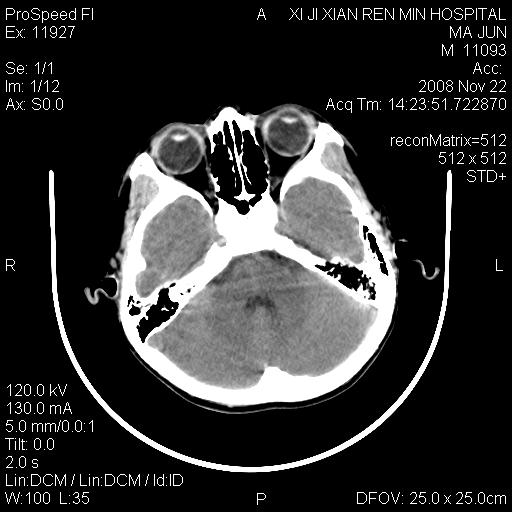

双侧侧脑室前角,三角区旁及半卵圆中心区白质呈低密度改变,半卵圆中心区病灶呈片状融合趋势,无软化征像,脑室无扩张,各神经核团无异常改变,脑皮质无萎缩等征像,结合病史考虑髓鞘发育不良性脑白质病,异染性脑白质营养不良可能性大.不除外多发性硬化等其他改变,建议磁共振检查

脑白质减少,双侧侧脑室额角旁及半卵圆中心可见对称性略低密度影,边缘尚清,考虑脑白质发育不良